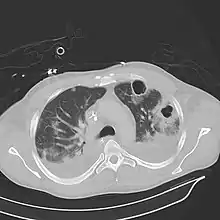

| Computed tomography (CT) scan of chest showing bilateral pneumonia with abscesses, effusions, and caverns. 37-year-old male. | |

Pulmonary abscess on CT scan